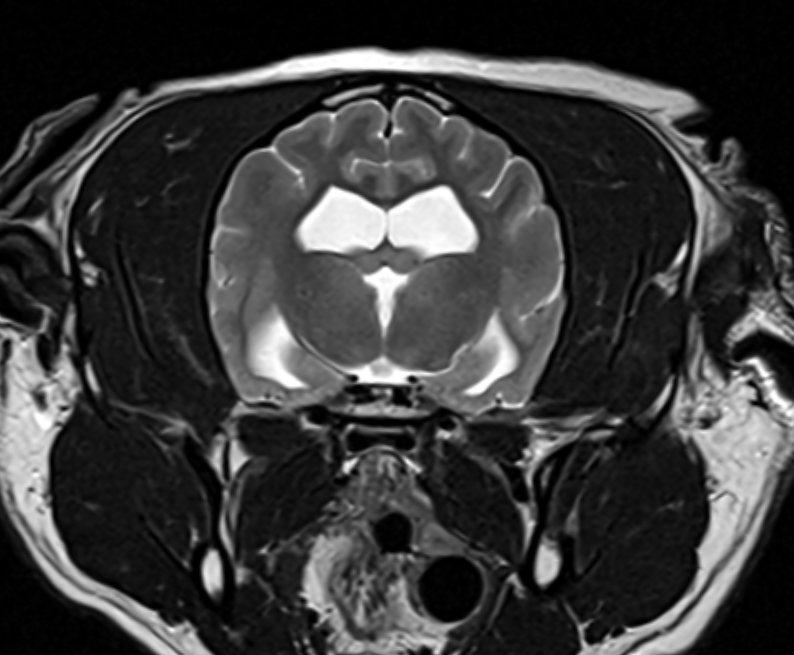

MRI

We have recently undergone software upgrades to our 1.5T MRI facility resulting in even greater image detail and reduced scan times, allowing reduced anaesthesia times for our patients. The quality of images of structures such as the brain, eye, spinal cord, and musculoskeletal system is exceptional.

We accept appropriate outpatient referrals for stable patients and perform a wide range of studies for our medicine and surgery service inpatients. For more information about our MRI service, you can call or email the Radiology department and speak with our MIT, charge nurse or radiologists.